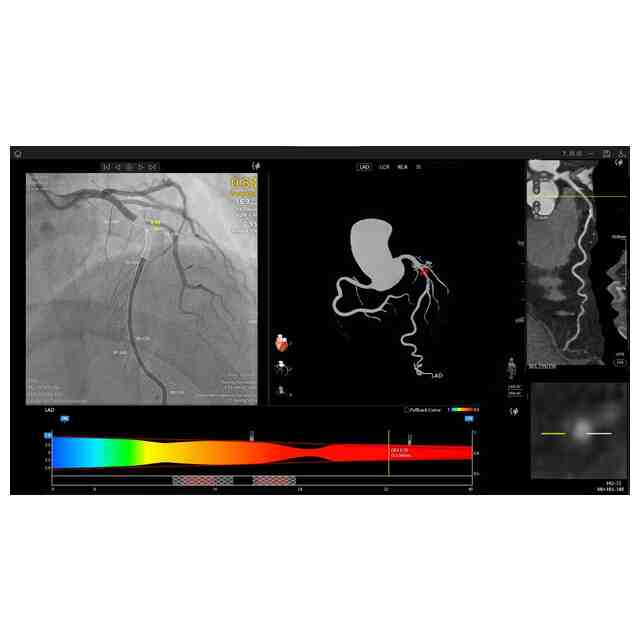

画像図及び変化後を示す画像図1~3は、例えば、複数の医療用画像を登録した後に表示して分析するために用いられる。使用状態を示す参考図1~6、変化後を示す画像図1の使用状態を示す参考図1~5、変化後を示す画像図2の使用状態を示す参考図、及び、変化後を示す画像図3の使用状態を示す参考図は、医療用画像データを分析するに際し、表示される図を示したものである。変化後を示す画像図1は、画像図における下方において黄色で示されたウインドウの右上隅にある「非表示」ボタンが押されると表示される画像である。変化後を示す画像図2は、変化後を示す画像図1における黄色で示された左端のウインドウがダブルクリックされると表示される画像であり、変化後を示す画像図2における黄色で示されたウインドウがダブルクリックされると画像図に戻る。変化後を示す画像図3は、画像図における黄色で示された中央のウインドウがダブルクリックされると表示される画像である。

図面中、黄色で示された部分以外の部分が部分意匠として意匠登録を受けようとする部分である。